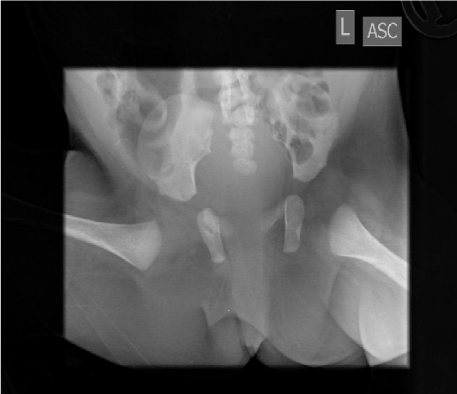

One female with caudal regression syndrome need clean intermittent catheterization and from time to time because of severe chronic recurrent anal sores need hospital care (Figure 2). Her fecal incontinence was managed via daily wash-outs.

Figure 2. Abscence of the coccyx, caudal regression syndrome.